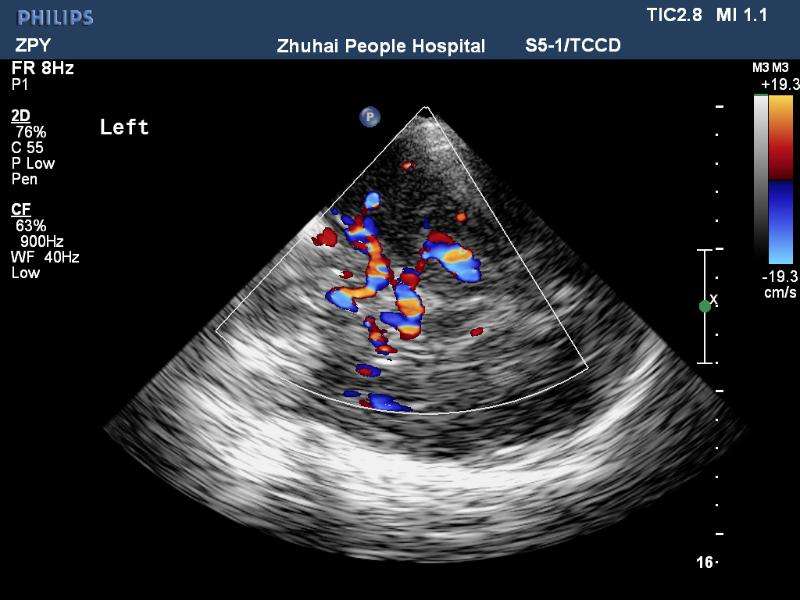

經(jīng)顱彩色編碼雙功能超聲(transcranial color-coded duplex sonography

TCCD)是一種非侵入性發(fā)現(xiàn)顱內(nèi)動脈異常血流動力學(xué)狀態(tài)的可靠方式。TCCD成像原理是在TCD基礎(chǔ)上增加了二維灰階實時顯像以及彩色編碼雙功能超聲成像,在二維顯示顱內(nèi)解剖結(jié)構(gòu)的同時,同時對運動紅細(xì)胞產(chǎn)生的多普勒頻移進(jìn)行彩色編碼。應(yīng)用TCCD檢測時可以通過在感興趣區(qū)內(nèi)多點取樣,得出取樣容積內(nèi)多普勒頻移曲線,通過雙側(cè)對比、左右對比以及前后對比,綜合評價缺血性腦血管病受檢者Willis環(huán)的血流動力學(xué)變化。

TCCD成像圖片

TCCD成像模式

依據(jù)多普勒頻移值編碼成像即f-TCCD:依賴運動紅細(xì)胞所產(chǎn)生的多普勒頻移值進(jìn)行計算機(jī)編碼,可以顯示血流方向和測算血流速度,需要校正多普勒取樣角度,角度及篩查深度依賴性較大,較易產(chǎn)生運動偽像。(2)依據(jù)運動紅細(xì)胞所產(chǎn)生的總能量進(jìn)行編碼成像即p-TCCD:只與運動紅細(xì)胞所產(chǎn)生的總能量有關(guān),無需校正多普勒取樣角度,對于受取樣角度影響較大血管病變,諸如大腦后動脈(PCA),大腦中動脈(MCA)M2段,大腦前動脈(ACA)A1段有一定的幫助作用,信噪比更高,不易產(chǎn)生混疊效應(yīng)。p-TCCD相對f-TCCD而言,缺點是不能顯示血流方向,對顯示狹窄處高速血流敏感性較低。